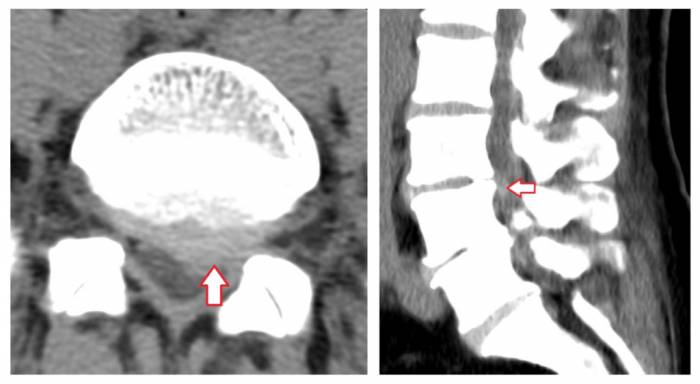

Грыжи межпозвонковых дисков при КТ позвоночникаклассифицируются в зависимости от их локализации. Так, выделяют задние, латеральные и передние грыжи дисков — в зависимости от того, в какую сторону выпадает межпозвонковый диск. Задние грыжи в свою очередь могут быть центральными (диск выбухает кзади по средней линии), медиаолатеральными (диск выбухает в латеральный карман справа либо слева), фораминальными (диск выбухает в межпозвонковый канал). Грыжа диска может быть также внутрикостной (по типу т. н. грыжи Шморля) — при этом происходит пролабированиепульпозного ядра в тело позвонка с проламыванием его замыкательной пластинки.Грыжа Шморля при компьютерной томографии позвоночника выглядит как дефект тела позвонка, отграниченный плотным склерозированным «ободком». Редко встречается также вариант интрадурального пролапса (грыжи), когда секвестр распространяется под твердую оболочку спинного мозга.

Пример парамедианной грыжи межпозвонкового диска в пояснично-крестцовом сегменте позвоночника при компьютерной томографии (грыжа диска отмечена стрелкой). В диске визуализируются также включения газа («вакуум-фемонен»), отмечены красной звездочкой «*».